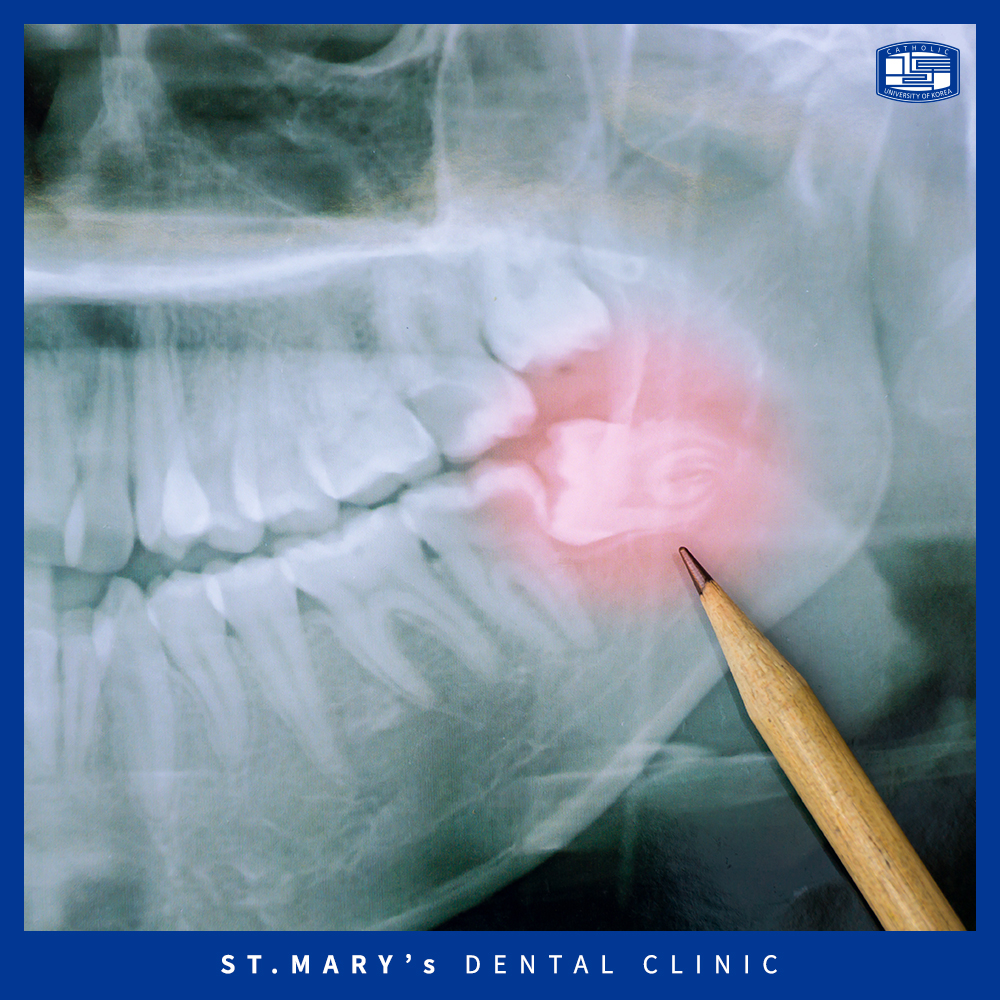

바로 비정상적인 형태로 맹출한 경우입니다.

앞서 언급했듯이 입 안 깊숙한 곳에서 가장 늦게 나타나는데,

좁은 공간을 비집고 나와 옆으로 누워서 맹출하거나

잇몸 속 안에 매복되어 나타나곤 하는데요.

비정상적인 형태를 띠고 있는 치아는

인접치의 신경을 계속 자극하고 압력을 가해

치열에 변형을 줄 수 있으며,

잇몸 안에 매복되어 있는 경우에는

낭종이나 양성 종양이 발생할 수 있습니다.

위와 같은 경우에는 아프지 않아도 문제를 일으키기 때문에

의정부치과에서 사랑니발치를 진행하는 것이 ⭐필수⭐